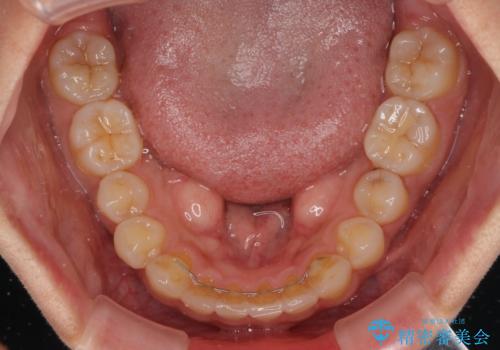

【モニター】歯列が狭くデコボコが気になる 急速拡大装置を用いたインビザライン矯正

上顎骨の幅が下顎骨よりも小さいので、拡大装置により骨幅を広げて上下関係を改善し、その後インビザラインにて歯並びを整えることとしました。

矯正治療後には土台のままとなっている歯をセラミッククラウンにて補綴治療を行うこととしました。

上下の骨幅を改善したことで、スムーズに歯列矯正を行うことができました。

土台のまま放置されていた歯は土台の状態で咬み合っていましたが、急速拡大を行った際に咬み合わせが著しく挙上されたため、その際に土台を大きくすることで咬み合う歯との距離を確保しました。